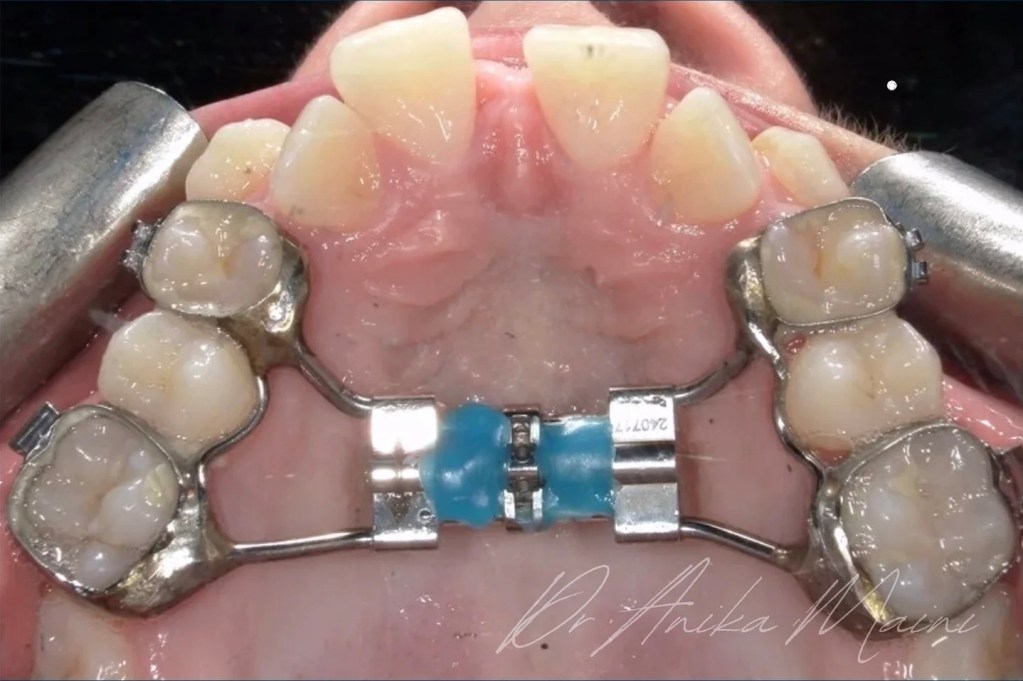

Os dispositivos mais utilizados incluem expansores do tipo Hyrax, Haas e suas variações contemporâneas, além de aparelhos assistidos por mini-implantes.

A instalação deve garantir estabilidade, adaptação passiva inicial e correta distribuição das forças.

Uma instalação inadequada compromete tanto a eficiência da expansão quanto o conforto do paciente, além de aumentar o risco de efeitos colaterais.

Após a instalação, inicia-se a fase de ativação do parafuso expansor.

O protocolo clássico envolve ativações diárias ou semi-diárias, conforme o planejamento individualizado.

Cada ativação promove um afastamento progressivo das hemi-maxilas.

Essa etapa exige orientação clara ao paciente ou responsável, especialmente quando as ativações são realizadas em ambiente domiciliar.

O controle clínico frequente é indispensável para monitorar a resposta tecidual e evitar sobrecarga.

Pressão do aparelho

Durante a fase ativa, o aparelho exerce pressão significativa sobre as estruturas ósseas e dentárias.

Essa pressão é responsável pela abertura da sutura palatina e pela resposta adaptativa do complexo maxilar.

Clinicamente, observa-se o surgimento de um diastema interincisal, considerado um sinal clássico de disjunção sutural efetiva.